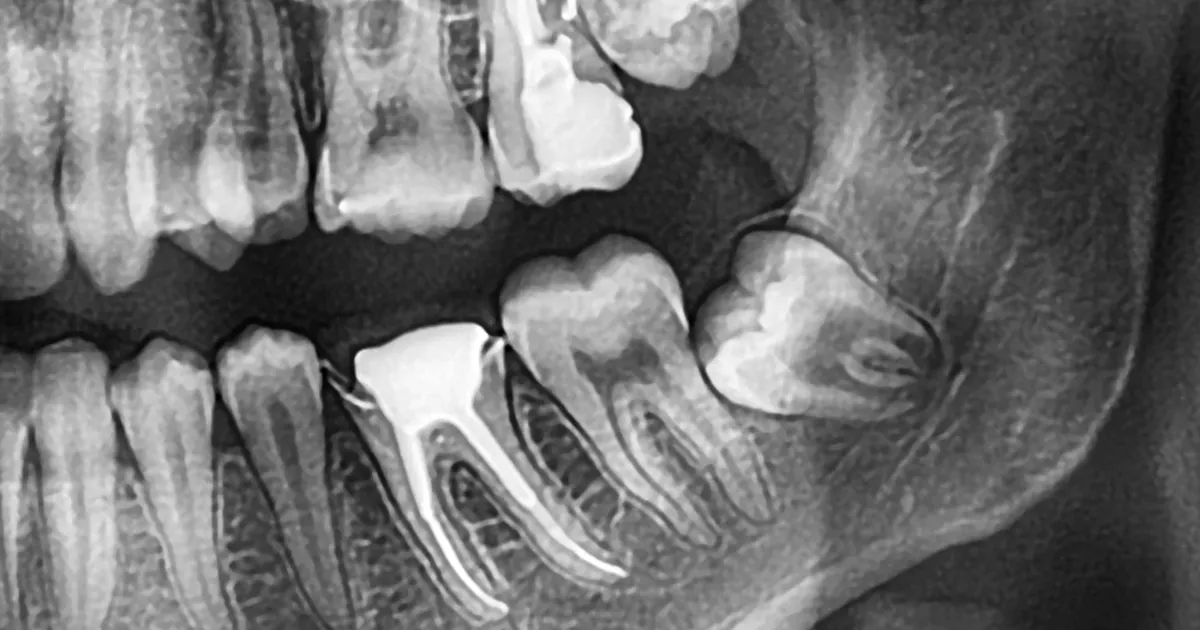

在下颌部拔除智齿时,如果牙齿位置接近神经,可能会引发麻痹。齿科哈米尔高田88使用CT扫描精确定位神经,尽量减少这种风险。